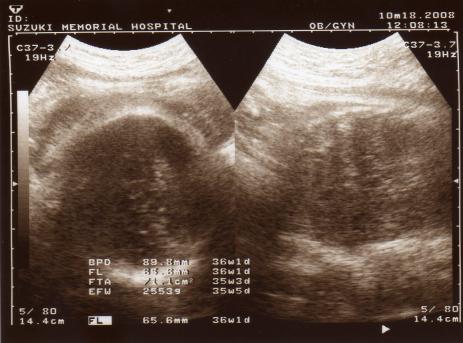

36週です 何かこのエコー 口がおかしくないですか 先生からはなんに Yahoo 知恵袋

胎児の推定体重まさかの4kg超え 難産覚悟で迎えた出産だったけど ガジェット通信 Getnews

妊娠38週0日 38w0d の超音波 エコー 写真

妊娠38週0日 38w0d の超音波 エコー 写真